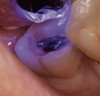

A 70-year-old patient presented with symptoms of a cracked tooth scenario, with intermittent pain upon chewing and thermal sensitivity. The diagnosis was supported through various tests, which determined the lower right second molar had an incomplete fracture that extended from the distal marginal ridge to the mesial marginal ridge. After treatment options were presented, an all-ceramic restoration was decided upon. The tooth was prepared for a nonretentive, adhesively retained all-ceramic restoration ("table top" preparation) (Figure 2 and Figure 3). After the preparation was completed a mild self-etching adhesive was applied to the dentin according to the manufacturer's instruction (Figure 4). There was little concern, if any, of the adhesive reaching the band of exposed enamel. The adhesive was light-polymerized for 5 seconds to secure the layer to the dentin (Figure 5). To eliminate the oxygen-inhibited layer a water-soluble gel was applied to the adhesive and further light-polymerization was completed (Figure 6 and Figure 7). For direct digital scanning cases in which a powdering technique is employed for image capture, it may be more difficult to remove the powder after scanning if the oxygen-inhibited layer is still present.

Figure 4  Application of a self-etching adhesive immediately after completion of tooth preparation.

Figure 4

Figure 5  Adhesive layer initially light-polymerized for 5 seconds.

Figure 5

Figure 6  Application of water-soluble gel to block oxygen from adhesive layer.

Figure 6

Figure 7  Elimination of oxygen-inhibited layer by light-polymerizing adhesive through the layer of glycerin material.

Figure 7